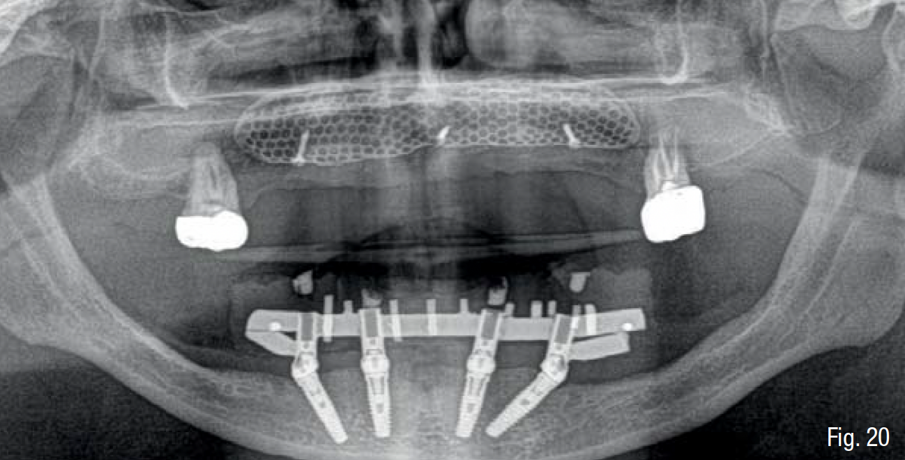

Infine, è stata eseguita un’attenta chiusura di prima intenzione dei lembi chirurgici, mediante una sutura a doppio strato, costituita da una linea di punti a materassaio orizzontale e da una linea di punti staccati singoli, per garantire una chiusura ermetica della ferita (SERAFAST 5/0, Serag-Wiessner, Naila, Germany) (Figg. 18, 19). Nei 7 giorni consecutivi il paziente ha proseguito la terapia antibiotica a base di amoxicillina e acido clavulanico e una terapia antiinfiammatoria a base di nimesulide; risciacqui con clorexidina 0.20% 3 volte al giorno per 2 settimane; e non ha utilizzato la protesi parziale rimovibile sempre per 2 settimane. Dopo 9 mesi, essendo stata confermata una sufficiente mineralizzazione del volume osseo al di sotto della griglia mediante una CBCT post-operatoria (Figg. 20-22), è stata pianificata una chirurgia computer-guidata per inserire gli impianti in modo protesicamente guidato (Figg. 23, 24).